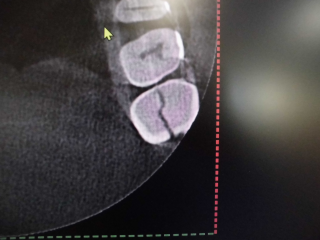

上顎洞との位置関係が確認できます。

CTでは近心の第二根管も確認できます。